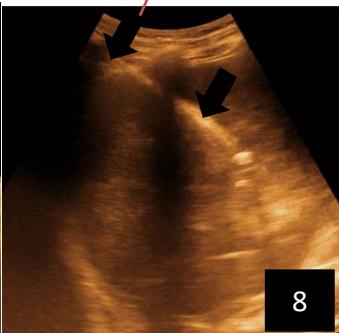

Iconography 1: 54-year-old patient with an intra-splenicsolid mass, anatomopathologically compatible with lymphoma: images 1 and 2: right pleurisy of moderateabundance, image3: celiacadenopathy, image 4: free ascites of moderateabundance, images 5 and 6: intra-splenicsolid mass of around $1418.16\mathrm{ml}$ in B mode and elastographyshowing areas of tumourrigidity, images 7-10: oblique linear images, showingbiopsy gun tracks.

Iconography B: 1 to 4: ultrasound images in mode B showing a large size, 5: ultrasound image in mode B showingsolidhyperechogenic nodules under the capsulorhexis, 6 to 10: ultrasound images in mode B showinglinearhyperechogenic images without overlay in relation to the trajectories of the aiguilles of biopsy.